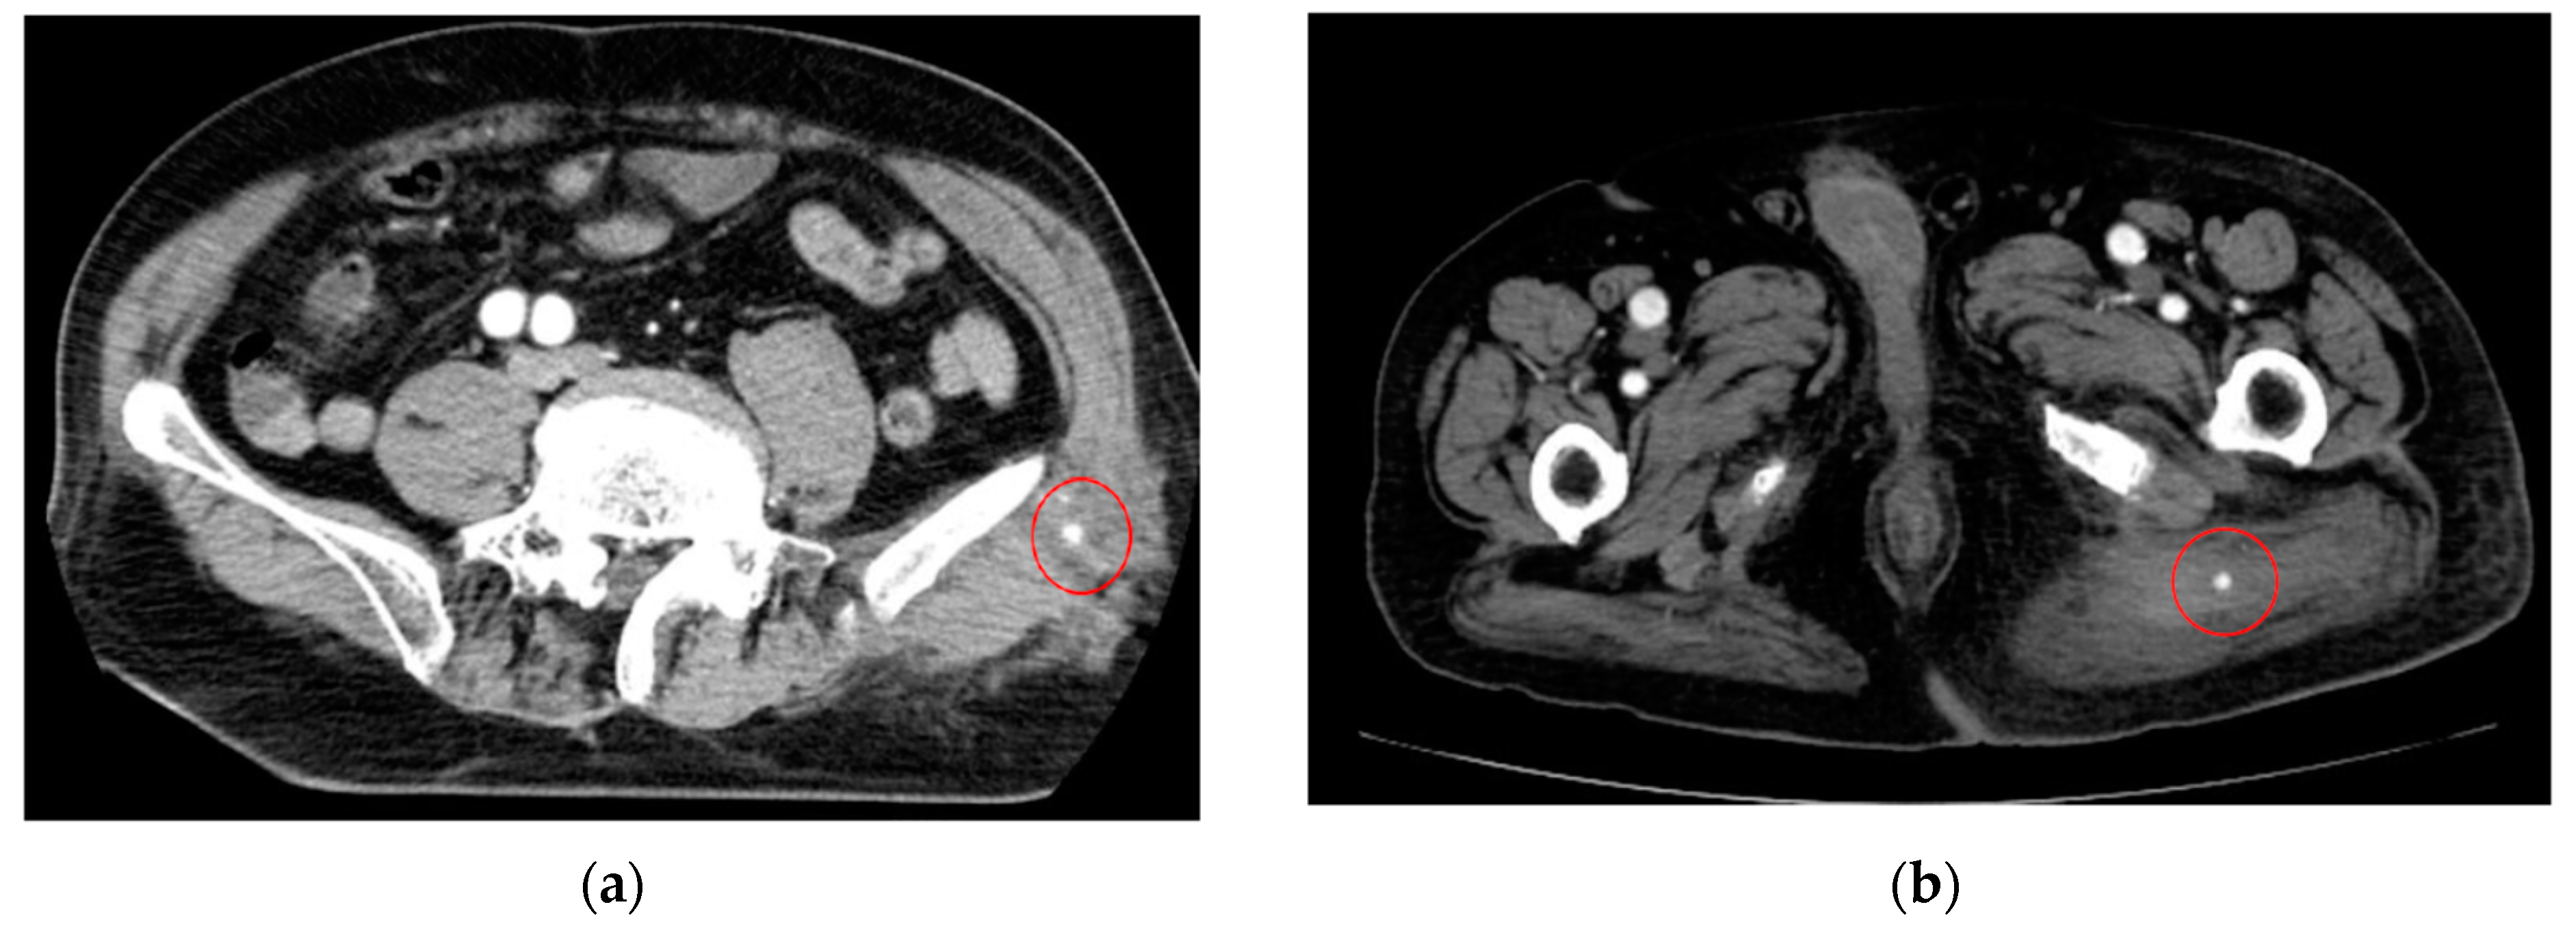

As an example, Figure 1 shows extravasation-induced hemorrhage from a polycystic kidney. Identifying the precise bleeding site on the computed tomography (CT) image presented a challenge. However, upon reviewing the angiography findings, it became evident that the bleeding originated from the area depicted in the CT image. In Figure 2, two instances of extravasation-induced hemorrhage are depicted, marked with the circles. Firstly, (a) displays a pseudoaneurysm visible post-spleen injury. Secondly, (b) illustrates a muscle hematoma in the chest region. In Figure 3, two cases of extravasation-induced hemorrhage are evident. In (a), circles mark extravasation on a fractured pelvic region, indicating a significant injury. Meanwhile, (b) showcases an intragluteal hematoma, highlighting the varied presentations of extravasation across different anatomical contexts. These CT images provide valuable insights into the varied presentations of extravasation cases across different anatomical contexts.

Figure 3.

Extravasation-induced hemorrhage marked with circles on fractured pelvic (a) and intragluteal hematoma (b).